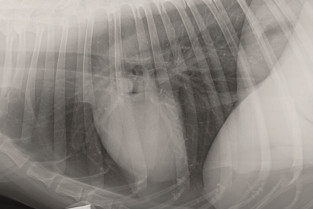

Celle-ci sera entièrement consacrée à l'imagerie du thorax chez le Chien et le Chat. Elle se veut résolument pratique et vous permettra avant tout de mieux choisir votre examen complémentaire d'imagerie lors de pathologie thoracique. Et surtout d'en tirer tous les renseignements utiles pour avancer dans votre diagnostic et dans la prise en charge de votre patient.

- d'optimiser les réglages de son appareil de radiologie pour obtenir un cliché thoracique de qualité chez le Chien et le Chat ;

- d'interpréter les différentes images physiologiques et pathologiques de la radiographie thoracique ;

- d'acquérir des images échographiques de qualité au niveau du thorax et de les interpréter ;

- de décrire les apports de l'imagerie tridimensionnelle, scanner et IRM à la radiographie et de l'échographie thoracique.